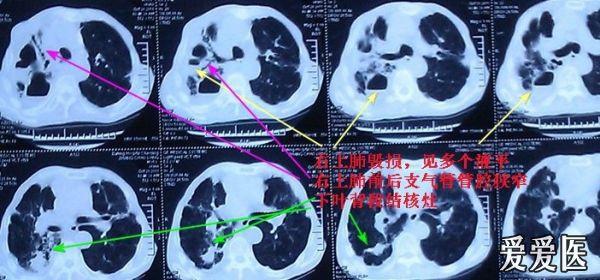

1.咳嗽伴发热多见于急性上、下呼吸道感染、肺结核、胸膜炎等。

2.咳嗽伴胸痛常见于肺炎、胸膜炎、支气管肺癌、肺栓塞和自发性气胸等。

3.咳嗽伴呼吸困难见于喉水肿、喉肿瘤、支气管哮喘、慢性阻塞性肺病、重症肺炎肺结核、大量胸腔积液、气胸、肺淤血、肺水肿及气管或支气管异物。

4.咳嗽伴咯血常见于支气管扩张、肺结核、肺脓肿、支气管肺癌、二尖瓣狭窄、支气管结石、肺含铁血黄素沉着症等。

5.咳嗽伴大量脓痰常见于支气管扩张、肺脓肿、肺囊肿合并感染和支气管胸膜瘘。

6.咳嗽伴有哮鸣音多见于支气管哮喘、慢性喘息性支气管炎、心源性哮喘、弥漫性泛细支气管炎、气管与支气管异物等。当支气管肺癌引起气管与支气管不完全阻塞时可出现呈局限性分布的吸气性哮呜音。

7.咳嗽伴有杵状指(趾)常见于支气管扩张、慢性肺脓肿、支气管肺癌和脓胸等。